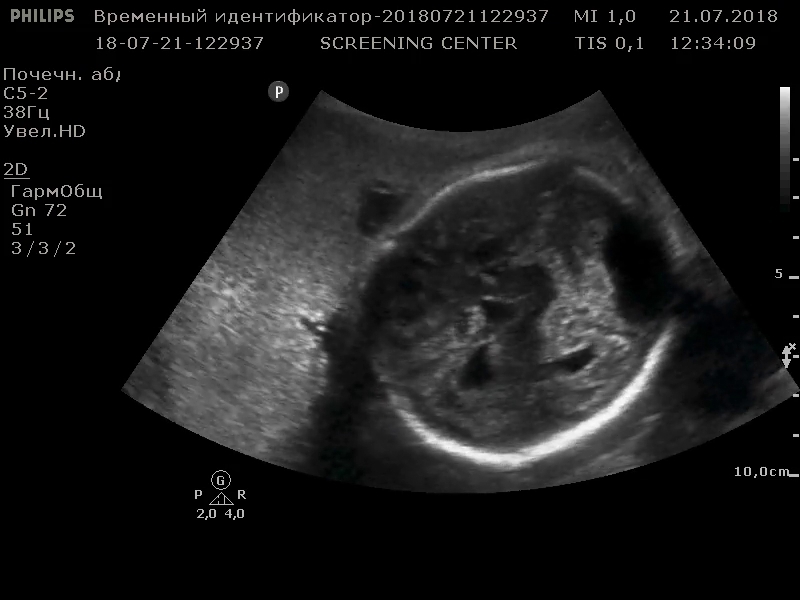

Норма скорости кровотока в вене Галена у детей до года — 4-18 см/сек . Среди изменений, которые наиболее часто выявляются в рассматриваемом сосуде, выделены: Аневризма вены Галена; Артериовенозная мальформация большой вены мозга . Аневризма вены Галена

Норма кровотока в вене Галена у детей от рождения до 1 года- 4-18 м/с . Анатомические особенности Анатомия вены Галена и ее особенности зависят от формы головы . В основном длина 12-14 мм . Форма черепа не влияет на ее диаметр в 5-7 мм . Глубокие сосуды проходят по всему мозгу и соединяются в самый большой и единственный проток . Общие симптомы

Нормальная скорость кровотока у детей до 1 года в вене Галена 4-18 см/с . Галенова вена может быть двух различных форм: магистральная и рассыпная . Первая из них имеет длину ствола 1,5-3 см, и не . . .

Длина сосуда у новорожденных варьируется от 12 мм до 2 см в зависимости от строения черепа . Диаметр сосуда редко превышает 5 мм, но официальная норма допускает ширину сосуда до 7 мм . При таких размерах скорость кровотока в вене достигает 18 см/сек . Основная функция сосуда — транспортировка крови в яремное венозное сплетение .